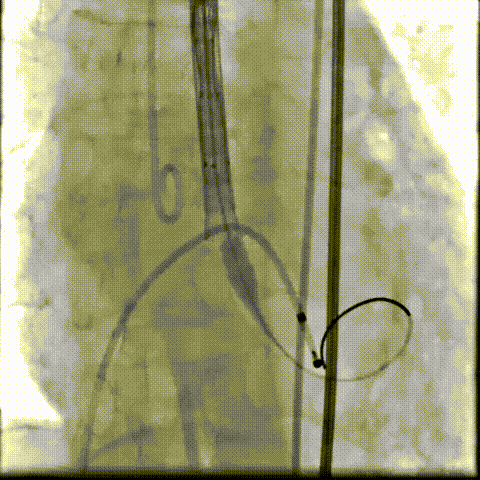

术中影像

根部造影可见返流,23mm球囊预扩张

无窦侧严重钙化及融合影响,

瓣膜(AV29)释放不稳出现反复上跳,2次回收尝试

重新定位释放,

钙化及融合挤压导致瓣膜(AV29)下滑位置偏深

第三次回收重新定位

工作位造影位置良好,完全脱钩释放瓣膜(AV29)

考虑支架腰部挤压,23mm球囊充分后扩后形态良好,

极微量瓣周漏